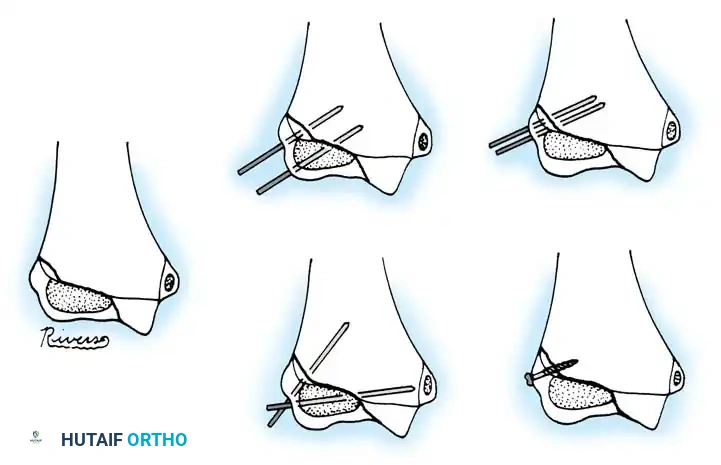

Percutaneous Leverage (Bernstein Technique)

Pesudo et al. and Bernstein et al. popularized the use of a percutaneous pin to manipulate the fracture fragments under fluoroscopy.

Anatomical Pitfall: During percutaneous reduction, the Kirschner wire must be introduced on the ulnar side of the radius. Introducing the wire laterally risks iatrogenic injury to the deep branch of the radial nerve (posterior interosseous nerve) as it traverses the arcade of Frohse.

Fig. 33-43 Radial neck fracture in relation to arcade of Frohse.

The Metaizeau Technique (Elastic Stable Intramedullary Nailing)

Gonzalez-Herranz et al. and Metaizeau revolutionized the treatment of displaced radial neck fractures (O’Brien types II and III) using retrograde intramedullary pinning. This technique boasts excellent results in over 94% of cases.

- Entry Point: A small incision is made over the distal lateral radial metaphysis, taking care to protect the superficial radial nerve.

- Pin Preparation: A steel Kirschner wire or titanium elastic nail (TEN) is sharply bent at the distal 1.5 cm.

- Insertion: The wire is advanced retrograde through the medullary canal until the bent tip engages the displaced proximal epiphysis.

- Reduction: The pin is rotated 180 degrees around its long axis. The bent tip acts as a cam, elevating the radial head and shifting it medially into anatomical position beneath the lateral condyle.

Fig. 33-44 A-D, Reduction of radial head by leverage method and retrograde intramedullary pinning with Kirschner wire.